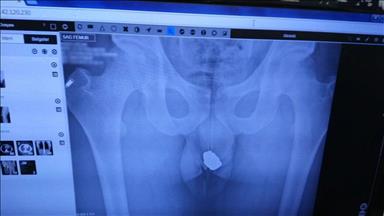

Burada ultrason ve röntgen filmi çekilen Özbilir'in yapılan endoskopi muayenesinde midesinde bir kol saati ve iki metal parçası olduğu belirlendi.

Hastanın midesindeki cisimlerin endoskopi bölümünde çıkarılamamasından dolayı hastayı ameliyat edeceklerini belirten Kalaycı, "Çekilen röntgen ve ultrason filmlerinde cisimler net bir şekilde görülüyor. Hastanın takiplerinde bir sıkıntı yok. Midesindeki cisimler ameliyatla çıkarılacak" dedi.